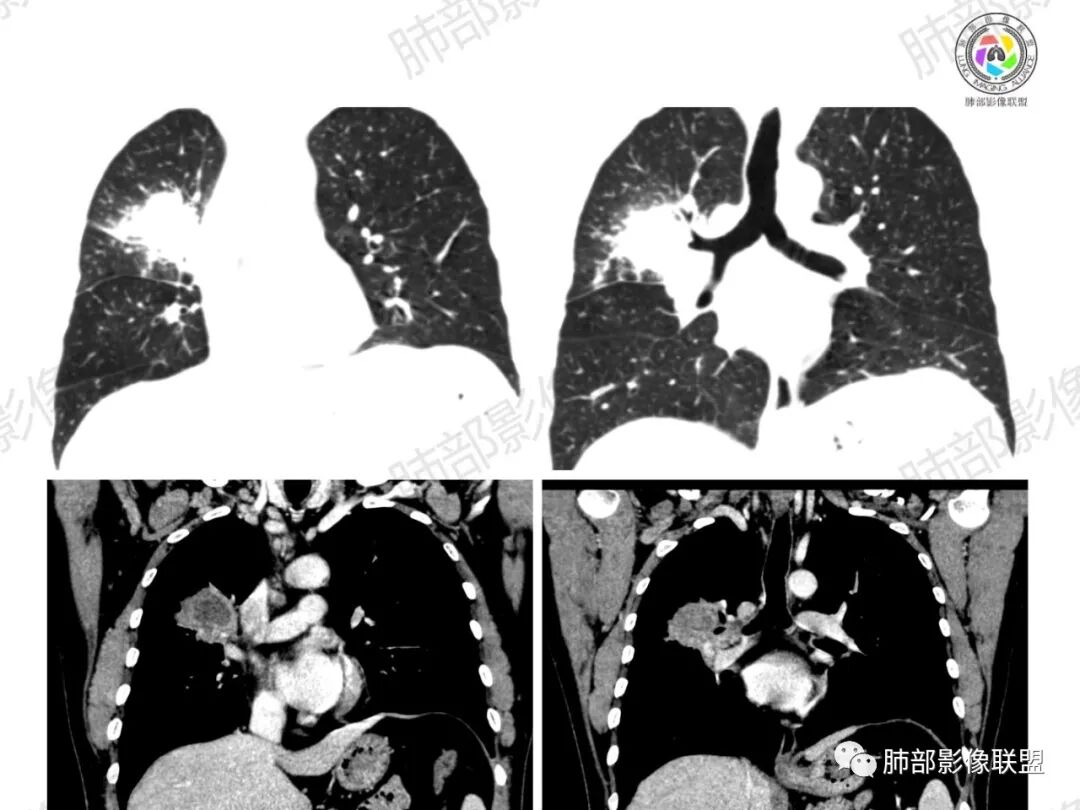

多发树芽,病灶边缘模糊的GGO

怎么看怎么不符合恶性,远端并不是明显的阻塞性炎改变,一是主要表现为树芽和结节,二是未按责任支气管分布。

1、坏死区内寸草不生;2、病灶环形强化;3、远端树芽和结节;4、远端不是阻塞性炎症,而是树芽和结节,右肺上叶前后段都有,后段为主,而堵塞的支气管应该是前段;这些树芽的位置不是堵塞支气管的责任区;5、支气管不是突然截断堵塞,而是逐渐狭窄;6、纵隔淋巴结是椭圆形增大,内有坏死,不是肿瘤的圆形饱满;7、支气管周围粘液样坏死,符合仙人掌结核改变;

3、阻塞性炎症:这个病例远端的散在病灶分布与责任支气管不符,所以不是阻塞性炎症,应该是树芽;

4、纵隔淋巴结肿大:这个病例的淋巴结肿大,不是圆形饱满,而是椭圆形,中间坏死。

所以,这个病例应先考虑炎性病变,以结核可能性大。慢性非特异性炎症伴脓肿形成,也可以这样的影像改变,但解释不了周围的树芽和结节。